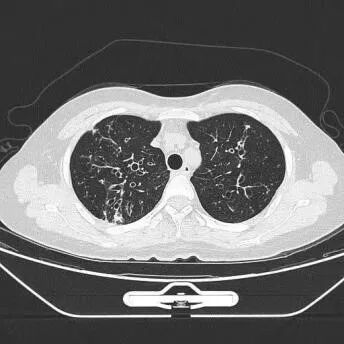

2.影像学检查:双肺支气管扩张并周边炎症

引起NTM肺病最常见的是脓肿分枝杆菌,好发于肺部已有基础疾病的患者,如慢性阻塞性肺疾病、支气管扩张症、囊性纤维化、尘肺病和肺泡蛋白沉着症等[6],常表现为慢性肺部疾病的恶化,也可有急性发病。脓肿分枝杆菌为条件致病菌,可通过皮肤、呼吸道等途径侵入人体,其病程与结核病相似,临床症状与肺结核亦相仿,如发热、盗汗、乏力、咳嗽、咯血等,胸部影像学表现也相似,其影像学以多发支气管扩张、薄壁空洞为特征性改变,同时伴有细支气管炎、多发微结节、树芽征及局部肺实变,仅仅依靠临床症状与胸部影像学表现容易误诊。

本案例为一例抗酸染色阳性结核分枝杆菌rpoB基因和突变检测阴性,患者出院后培养鉴定为脓肿分枝杆菌,微生物工作人员及时与该患者主管医生联系并与患者及时沟通进行下一步治疗的案例。该患者影像学报告显示双肺支气管扩张并周边炎症,长期咳嗽咳痰,患者曾就诊外地专科医院行培养后考虑诊断非结核分枝杆菌病,该病组织学上可分为四型:纤维空洞或类结核型、支气管扩张型、结节型及其他(肺纤维化、肺气肿、肺不张),结合以上类型考虑患者为支气管扩张性NTM。